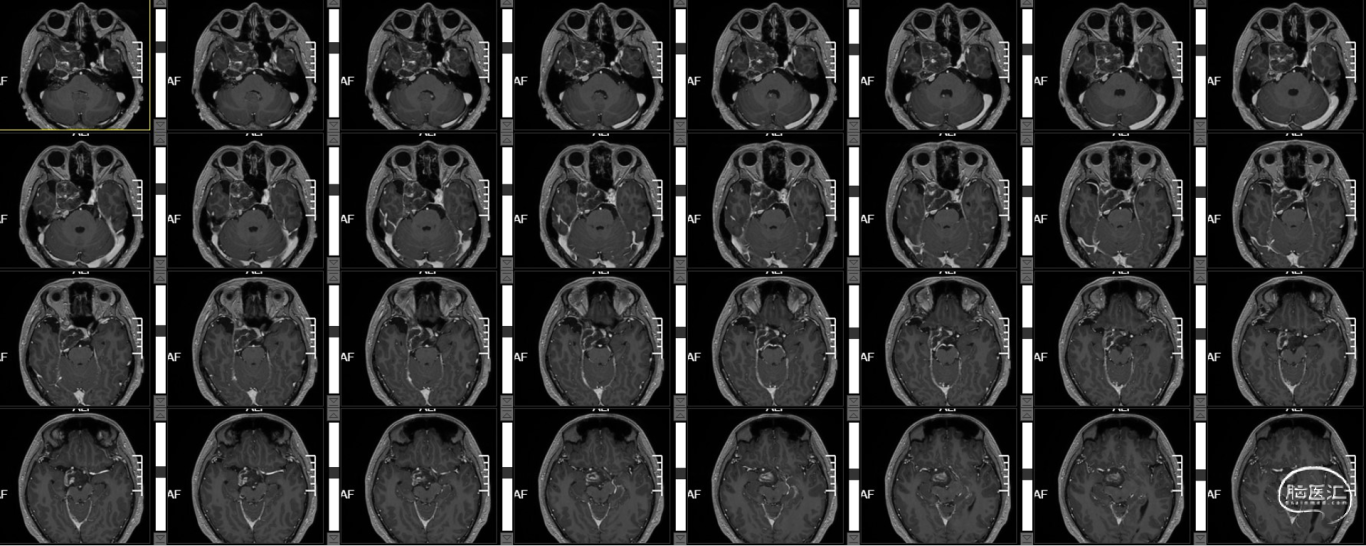

术前T1+C